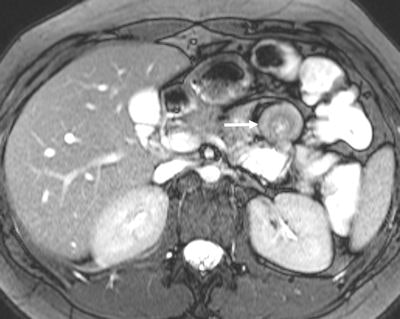

Among the bowel and mesenteric diseases to be aware of are internal hernia, intussusception, neuroendocrine tumor, and familial Mediterranean fever, all of which can mislead radiologists to erroneously diagnose active Crohn's disease, Kavaliauskiene stated. Often, knowledge of findings in these diseases can be sparse.

Biphasic oral contrast agents are the most frequently used contrast agents, according to Kavaliauskiene. Usually they have low signal intensity on T1-weighted images (optimizing the contrast between the enhancing bowel wall and hypointense lumen) and high signal intensity on T2-weighted images. Mannitol with tap water is often used as a biphasic agent. Intravenous contrast agents (gadolinium 0.1 ml/kg) are recommended for the assessment of inflammation of the small bowel and can be helpful for diagnosing other small bowel diseases as well.